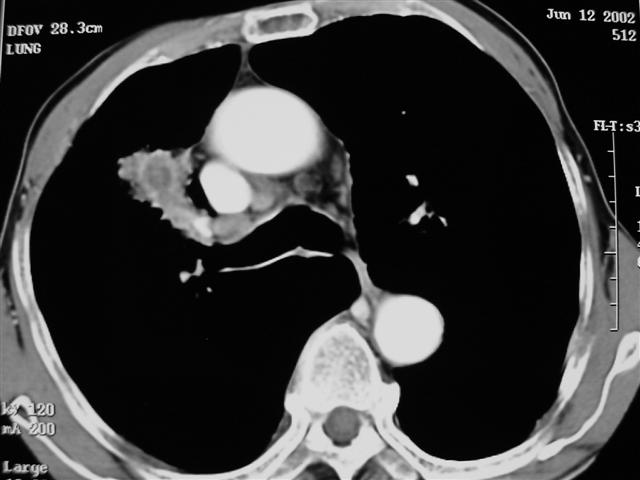

男,64岁,咳嗽、咳痰20余天,明显消瘦,x线片发现肺部阴影

长毛刺、肺门引流征象、中心液化坏死等应该是提示结核性肿块的可能性大,但是合并椎体及多处肋骨破坏则周围型肺ca并椎体及多处肋骨转移不能除外。

1)右肺上叶前段周围型肺癌并阻塞性肺炎、右肺门及纵隔淋巴结转移、肋骨及胸椎转移。2)右肺上叶后段纤维病灶。